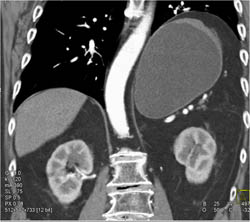

GIST Tumor